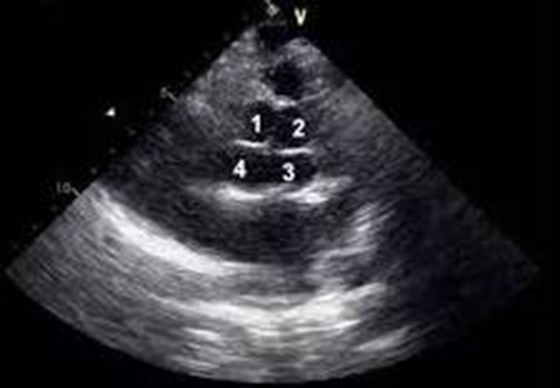

患者主动脉瓣四叶畸形在超声下的表现

术中,当切开主动脉时,豁然呈现主动脉瓣瓣叶呈四叶,其导致瓣叶关闭不全,瓣叶明显变薄。在麻醉与体外循环的配合下,心胸外科团队切除并置换了病变的主动脉及二尖瓣,三尖瓣则采用了精妙的Kay’s成型术,整个过程行云流水,生命体征全程平稳。